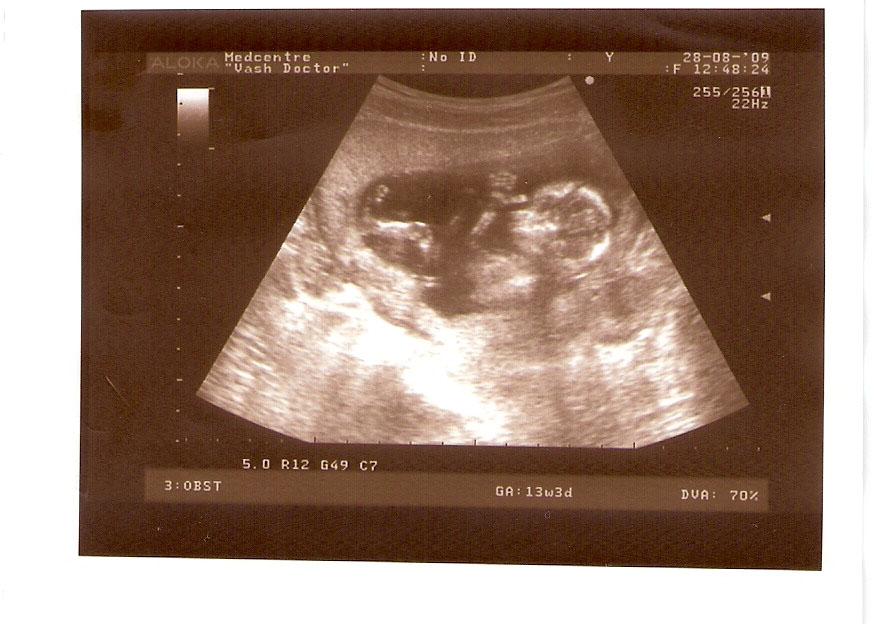

СЫН

| Вложения: |

2.jpg [ 110.14 КБ | Просмотров: 2625 ]

13 НЕД И 5 ДНЕЙ

3.jpg [ 96.81 КБ | Просмотров: 2623 ]

Nikisa писал(а): Foto prosto chudesnoe. A na kakom sroke uznali, chto sin.............. НА 13 НЕДЕЛЯХ.КАК РАЗ ВОТ В ЭТО узи, ОНО УМЕНЯ ВТОРОЕ БЫЛО. ЭТО КОНЕЧНО МАЛЕНЬКИЙ СРОК ДЛЯ ОПРЕДЕЛЕНИЯ ПОЛА. НО Я ПОПРОСИЛА ВРАЧА(ЭТО КТСТАТИВ РОССИИ БЫЛО) ХОТЯ БЫ ПРЕДПОЛОЖИТЬ. ЕЙ ВСЁ ТАКИ УДАЛОСЬ РАССМОТРЕТЬ.НУ ВООБЩЕМ ЧЕРЕЗ НЕСКОЛЬ ДНЕЙ ПОЙДУ К ВРАЧУ, УЖЕ АМЕРЕКАНСКОМУ И УЗНАЮ ТОЧНО. К ТОМУ ВРЕМЕНИ У МЕНЯ БУДЕТ СРОК 18 НЕДЕЛЬ. ХОТЕЛОСЬ БЫ ПОСМОТРЕТЬ НА ДРУГИЕ ФОТО НА ЭТОМ СРОКЕ ИЛИ БОЛЬШЕ. ТАК ЧТО ВЫКЛАДЫВАЙТЕ, ЕСЛИ НЕ ЖАЛКО!